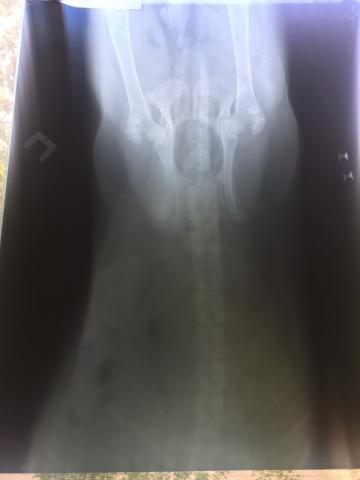

Здравствуйте! у нас щенок спаниеля сейчас ему 7 месяцев. 1,5-2 мес назад он резко заболел. А именно: вечером был вялым , а с утра начал тягать задние лапы пока не расходится, отказался от еды( на него это ну никак не похоже). Не стали медлить и побежали к ветеринару. Он сказал что у нас парез и видимо его просквозило. температуры у собаки не было, анализ крови сдали. далее прокололи ему витамины группы б, дексаметазон, около 4 дней. после приема препаратов ситуация стала повторяться , обратившись к тому же ветврачу нам дали ответ что ему просто нужно попить минералов, купили. Дальше решили обратиться все таки к другому врачу. Его диагноз - дископатия. И у одного и у другого врача спрашивала не дисплазия ли это, ответ-нет. Вообщем начали лечение дургими препаратами,их прикреплою ниже. практически месяц давала ему преднизолон, сималджекс раз в три дня, 10 дней кололи витамины. по истчению и отмены лекарств собака далее начала снова тягать лапы.. сейчас сделали рентген, даем активет 2 т в день. я ношу его гулять по ступенькам на руках ,пытаюсь обеспечить полный покой , но щенок активный под препаратами. Я уже не знаю правильно ли мы его лечим или калечим всеми этими препаратми. Хотелось бы дополнить ,что пару раз брали его за горонд в 4 -5 мес где он бегал гулял целый день, также щенок любил спрыгнуть со всей силы на диван, на стул, со стула..Очень надеюсь на хоть малейшее предположение . Ах да , советовали делать миелографию но у нас в городе такого нет, ни кт , ни мрт. ближайший около 10 часов от нас, с собакой это нереально.